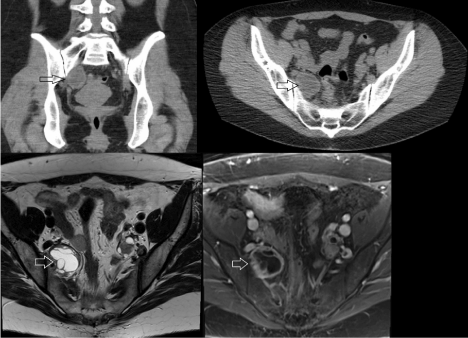

The patient is a 38-year-old woman who presented with a two-year history of back pain, right lower quadrant abdominal pain, and right buttock pain. Her medical history was unremarkable and surgical history included benign uterine polyp removal. Computed tomography (CT) of the abdomen/pelvis without contrast that demonstrated a 3.7 x 2.9 x 4.1 cm cystic lesion in the right posterior lateral pelvis (Figure 1). Of note, the patient had a prior CT of the abdomen/pelvis done 8 years earlier for abdominal pain that did not show the lesion. Magnetic resonance imaging (MRI) of the pelvis with contrast demonstrated that the multi-loculated, enhancing, cystic mass in the right upper pelvis was separate from the right ovary and contiguous with the R S1 nerve root (Figure 1). At this time, a diagnosis of cystic peripheral nerve sheath tumor was favored. She was referred to our office for further evaluation.

Figure 1. Pre-operative CT (top) and MR (bottom) imaging. Coronal (top left) and axial (top right) CT imaging of the lesion. The lesion, marked with an open arrow, had a hypodense center consistent with a cystic mass. T2 axial (bottom left) and T1 post-contrast (bottom right) MRI demonstrating the multi-loculated structure and contrast-enhancing rim of the lesion.